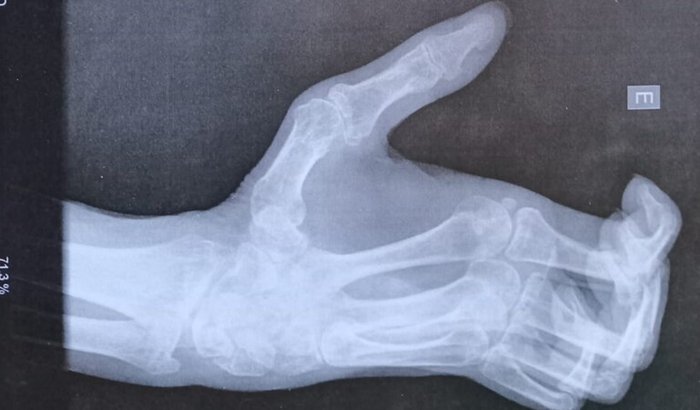

"A 3 anos sofri um acidente doméstico que fraturou o meu pulso com isso perdi os movimentos da mão esquerda como vão ver asseguir. Peço encarecidamente que contribuam para essa vaquinha virtual. Já tenho parte do dinheiro mas tá faltando uma quantia significativa. Quem se sentir tocado com a situação do AMIGO.

A CIRURGIA SERA FEITA EM DEZEMBRO POR UM MEDICO ESPANHOL ESPECIALISTA NESTES CASOS. SEM MAIS PARA O MOMENTO. MUITO  OBRIGADO DESDE JA. SEGUE A SEGUIR A DOCUMENTACAO.